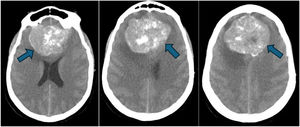

Cerebral CT scan was performed and revealed an occupying space brain lesion of 52.7 mm (Image 1, blue arrow) with edema. The patient was intubated and transferred to neurosurgery. Biopsy was made revealing a grade 1 meningioma. The patient was submitted to surgery and lesion was removed. At discharge, she was well without any neurological deficit.